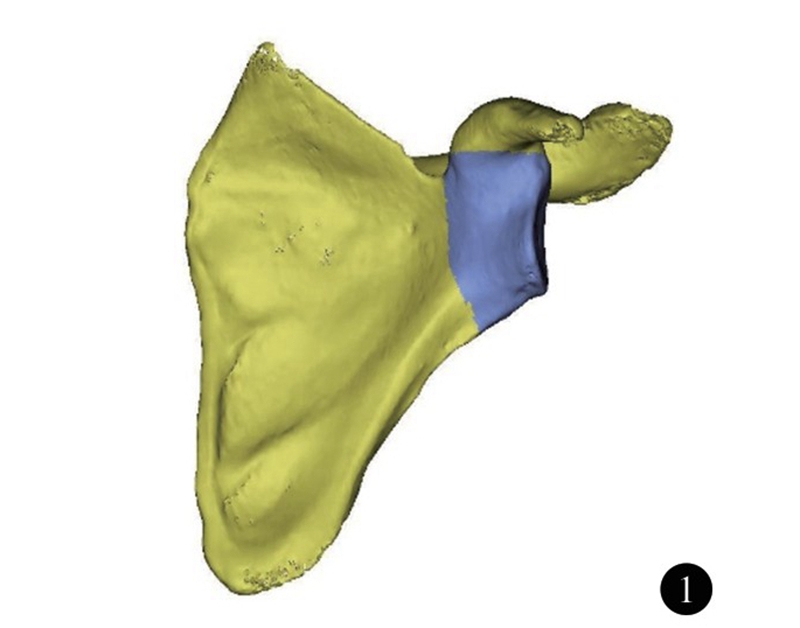

肩关节的活动主要由盂肱关节完成,为典型的球窝关节(杵臼关节) ,由肱骨头和肩胛盂构成。既往对肩关节的研究的重点集中在肩袖、关节囊韧带以及盂唇等结构,对肩关节的功能、稳定具有重要意义。随着中国社会老龄化的发 展,肩胛盂骨性结构改变所带来的问题日趋严重,包括关节盂的缺损、退变。因此,了解肩胛盂的正常解剖结构,有助于对肩关节复杂损伤、疾病的治疗。肩胛盂的解剖结构包括肩胛盂关节面以及肩胛盂体部。肩胛盂体部(glenoid vault) 是指肩胛骨包括肩胛盂表面及向内至肩胛冈外缘、喙突基底内缘的部分(图1) 。这一区域骨量少,位置深,结构复杂。虽然传统尸体解剖研究可用于测量肩胛骨表面解剖学参数,但难以精确描述和测量,尤其是肩胛盂体部。随着电子计算机技术的不断发展和三维重建技术的进步,对肩胛盂骨性解剖结构的测量有了新的方法。研究肩胛盂骨性解剖学结构,可为肩胛盂内固定物和肩关节假体设计提供指导依据。

图1 肩胛盂体部形态(深色部分) 示意图。包括肩胛盂表面及向内至肩胛冈外缘、喙突基底内缘的部分